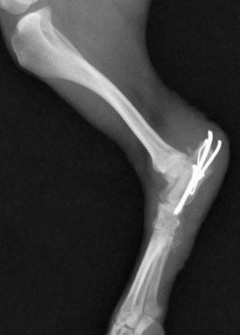

尺骨骨折を伴った肘関節脱臼

手術前レントゲン写真

手術後レントゲン写真

手術中の肘関節の写真